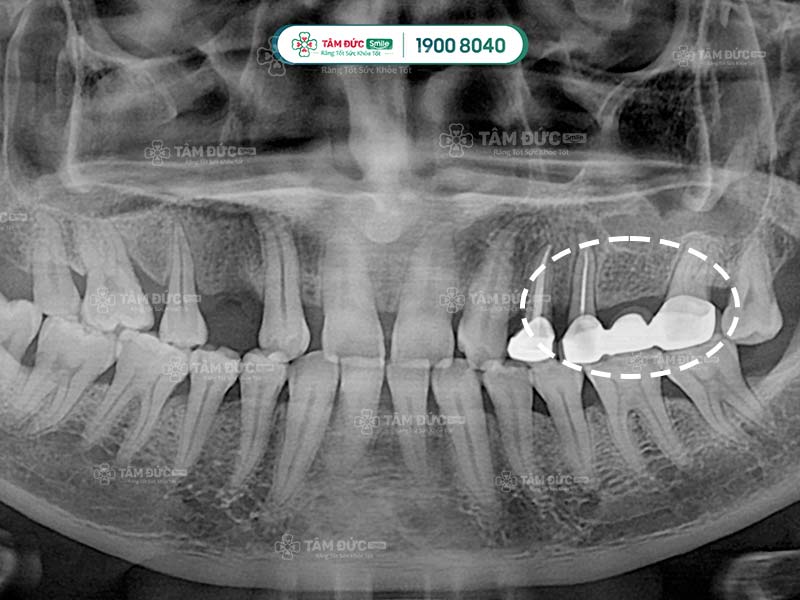

Bác sĩ tiến hành mài 2 cùi răng bên cạnh để tạo 2 trụ, làm điểm tựa cho 3 răng sứ để thay thế cho chiếc răng bị mất.

Cầu răng sứ có ưu điểm là thời gian thực hiện nhanh chóng, chi phí thấp hơn cấy ghép Implant. Tuy nhiên, phương pháp này cũng có nhược điểm là làm tiêu xương hàm, gây tụt lợi và biến dạng khuôn mặt.

Cầu răng sứ qua phim X-Quang